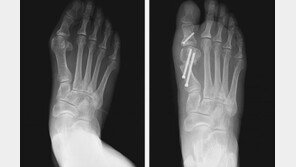

여름철이면 적지 않은 족부질환 환자들이 병원을 찾는다. 건강보험심사평가원에 따르면 2018년부터 3년 간 무지외반증, 족저근막염 등 족부질환으로 병원을 찾은 환자는 6∼8월에 47만1145명으로 가장 많았다. 대표적인 족부질환인 무지외반증과 족저근막염의 치료법에 대해 박유정 목동힘찬병…